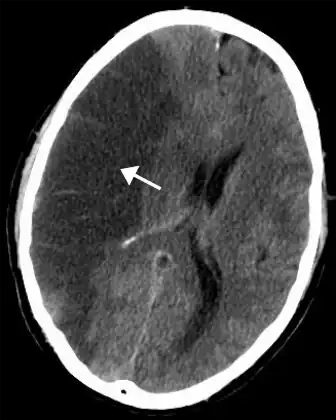

For diagnosing ischemic (blockage) stroke in the emergency setting:[69]

- CT scans (without contrast enhancements)

- sensitivity= 16% (less than 10% within first 3 hours of symptom onset)

- specificity= 96%

- MRI scan

- sensitivity= 83%

- specificity= 98%

For diagnosing hemorrhagic stroke in the emergency setting:

- sensitivity= 89%

- specificity= 100%

- sensitivity= 81%

For detecting chronic hemorrhages, an MRI scan is more sensitive.[70]

CT scans may not detect ischemic stroke, especially if it is small, of recent onset,[10] or in the brainstem or cerebellum areas (posterior circulation infarct). MRI is better at detecting a posterior circulation infarct with diffusion-weighted imaging.[71] A CT scan is used more to rule out certain stroke mimics and detect bleeding.[10] The presence of leptomeningeal collateral circulation in the brain is associated with better clinical outcomes after recanalization treatment.[72] Cerebrovascular reserve capacity is another factor that affects stroke outcome – it is the amount of increase in cerebral blood flow after a purposeful stimulation of blood flow by the physician, such as by giving inhaled carbon dioxide or intravenous acetazolamide. The increase in blood flow can be measured by PET scan or transcranial doppler sonography.[73] However, in people with obstruction of the internal carotid artery of one side, the presence of leptomeningeal collateral circulation is associated with reduced cerebral reserve capacity.[74]